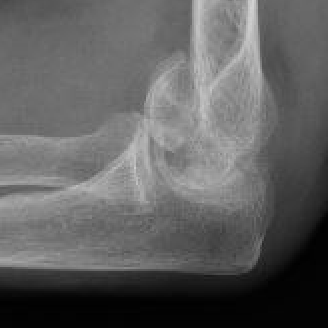

Double arc sign on xray |

Dubberly Classification

| Type I | Type Ii | Type III |

|

Capitellar fracture

Capitellum + trochlea fracture In one piece Double arc sign seen on xray |

Capitellum + trochlea fractures In two separate pieces |